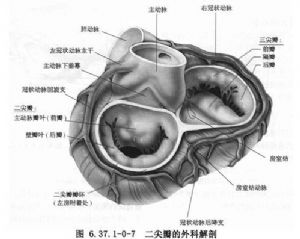

在瓣膜修复手术中,因为本病畸形的多样性,修复手术必须根据这些病理改变采用个性化手术。该手术是一种技术要求高、难度大的工艺性手术,需有经验的外科医生施行(图6.37.1-0-7~6.37.1-0-10)。